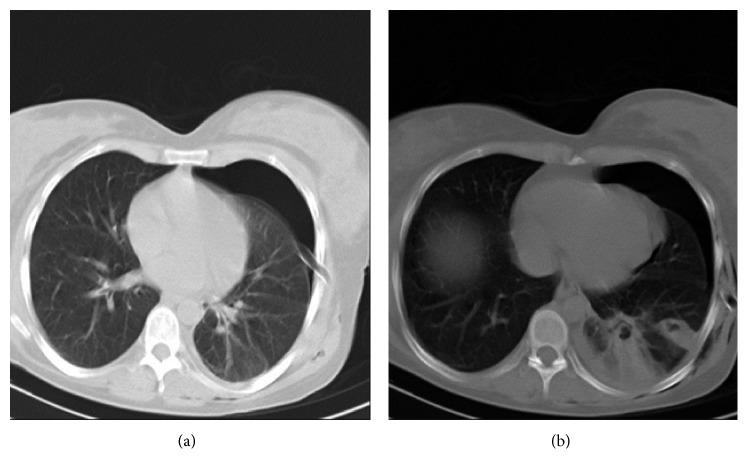

Necrotizing sarcoid granulomatosis (NSG) is a rare granulomatous pneumonitis which is composed of a background of sarcoidosis-like granulomas, granulomatous vasculitis, and variable amount of necrosis. We reported a case of a 38-year-old nonsmoking woman presented with left-sided chest pain and dyspnea for three days. Chest CT scan exhibited collapse consolidation of the left lower lobe with the presence of two separated small-sized cystic lesions within the collapsed segment. Lung lesion resection was performed, and histological examination confirmed the diagnosis by excluding other causes of granulomatous diseases. The prognosis of NSG is favorable, and medical treatment is usually not necessary, as well as in our case. NSG is a rare disease with nonspecific symptoms and good prognosis which is frequently confused with Wegener's granulomatosis, sarcoidosis, and Churg-Strauss syndrome. This entity should also be considered as differential diagnosis of necrotizing granulomatous diseases.

坏死性结节病样肉芽肿病(NSG)是一种罕见的肉芽肿性肺炎,由结节病样肉芽肿、肉芽肿性血管炎背景以及不同程度的坏死组成。我们报告了一例38岁不吸烟女性,出现左侧胸痛和呼吸困难3天。胸部CT扫描显示左下叶肺不张实变,在萎陷段内有两个分开的小囊性病变。进行了肺病变切除术,组织学检查通过排除肉芽肿性疾病的其他病因确诊。NSG的预后良好,通常无需药物治疗,我们的病例也是如此。NSG是一种具有非特异性症状且预后良好的罕见疾病,常与韦格纳肉芽肿病、结节病和变应性肉芽肿性血管炎综合征相混淆。该实体也应被视为坏死性肉芽肿性疾病的鉴别诊断。